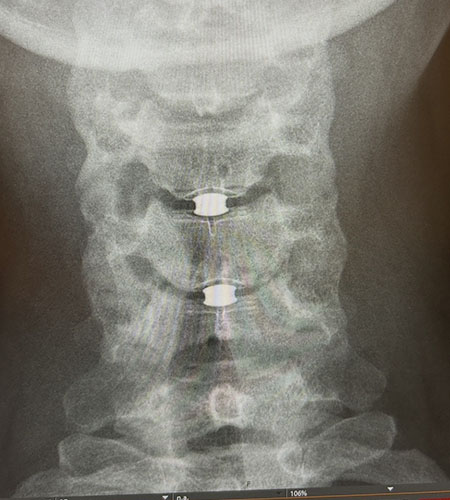

A scan of a woman's spine showing spinal implants.

A scan shows the new implants in Polach's spine after the surgery.

The synthetic discs consist of a ceramic core sandwiched between two plates of medical-grade plastic coated with titanium. Their dynamic cores allow for flexible movement of the spine. The device has been approved for replacement of up to two adjacent discs.

To install the replacement discs, Khan made a small incision in front of Polach’s neck and used a microscope and other precision instruments to remove the damaged discs. Under x-ray guidance, he sized the prostheses to relieve nerve pressure. He created small slots in her vertebrae and slid the new discs between them, ensuring their fit through imaging.